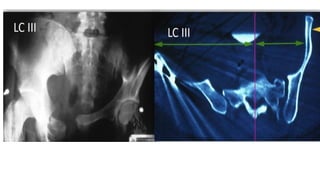

● Lateral compression ( LC)

○ LCIII. Ipsilateral LC and contralateral APC ( windswept pelvis)

● Lateral compression( LC) ○ LCI. oblique or transverse rami fracture and anterior sacral ala compression fracture ○ LCII. rami fracture and posterior ilium fracture dislocation ○ LCIII. Ipsilateral LC and contralateral APC ( windswept pelvis) ● Vertical shear ( VS) ○ Highest risk of hypovolemic shock and mortality